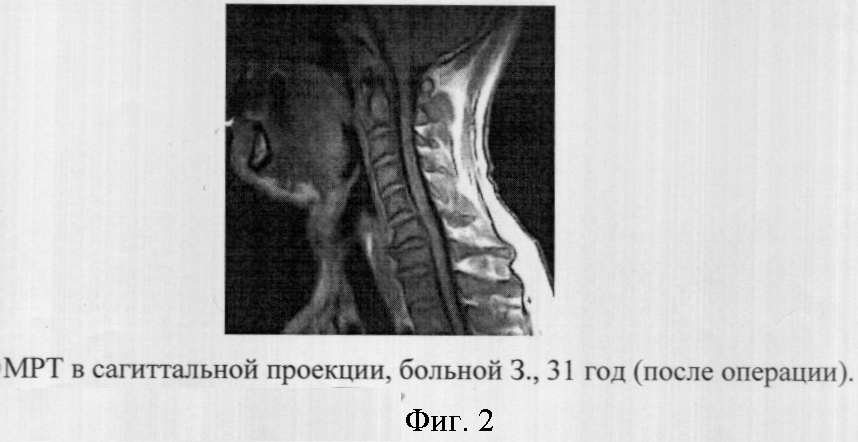

Пример 1. Больной 3., 31 год, находился на амбулаторном обследовании в ЛОР-отделении и отделении лучевой диагностики Амурской областной клинической больницы. В анамнезе у пациента храп в течение 5-ти лет. Ранее за медицинской помощью не обращался. После оториноларингологического осмотра и регистрации антропометрических показателей (индекс массы тела – 27,5 кг/м2, масса тела – 84,6 кг) пациенту для диагностики феномена храпа и последующей оценке результатов лазерной увулопалатопластики было рекомендовано проведение МРТ с определением объем мягкого неба и небного язычка, языка, носо-, рото- и гортаноглотки, площади сечения верхних дыхательных путей (фиг.1, 2). При МРТ использовалась напряженностью магнитного поля 0,35 Тесла, при сканировании с получением изображения по Т1 и техники сканирования SE2D, с TR от 470 до 550; ТЕ – 10; толщиной среза от 3,5 до 4 мм с шагом 0,2 мм и FOV – 22,4×22,4 или 25,6×25,6 см; максимальное разрешение (пиксель) при данных параметрах сканирования составило 1,0 мм2. Изображение оценивали на сагиттальных и аксиальных срезах, длительность исследования составляла 10 минут.

Через 2 месяца в ходе выполнения МРТ у данного больного было выявлено: объем мягкого неба – 5682,4 мм3, объем языка – 54941,2 мм3, объем носоглотки – 7472,1 мм3, объем ротоглотки – 16140,3 мм3, объем гортаноглотки – 8691,7 мм3, минимальная площадь верхних дыхательных путей в поперечном сечении – 106,9 мм2.

Сравнивая полученные результаты при МРТ у данного пациента до и после операции с результатами нормы объема мягкого неба и небного язычка, языка, носо-, рото- и гортаноглотки, площади сечения верхних дыхательных путей в поперечном сечении полученной при исследовании 30 здоровых человек мы пришли к выводу, что у данного пациента имеет место феномен храпа без синдрома обструктивного сонного апноэ, после выполнения пациенту лазерной увулопалатопластики данные показатели мягкотканых структур орофарингеальной области достоверно приближались к показателям нормы (таблица).